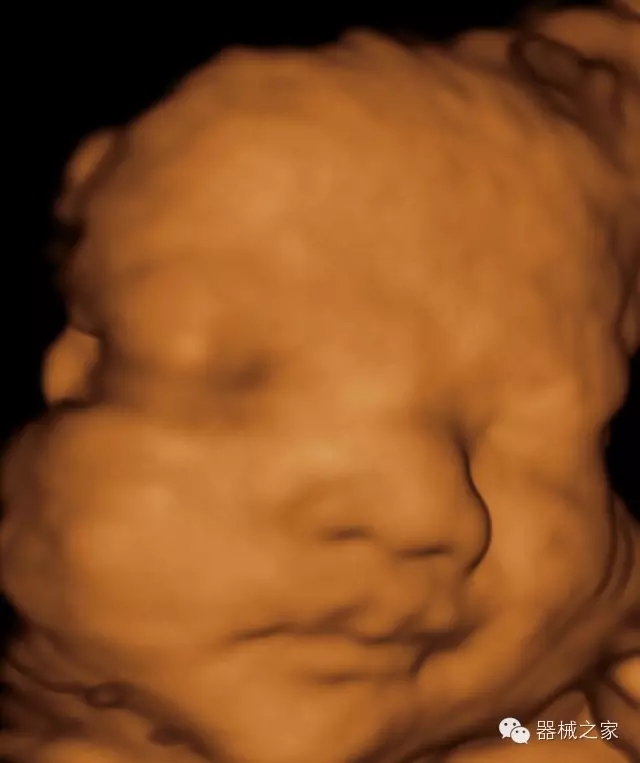

臨床圖片賞析

·完整的3D/4D臨床應(yīng)用,STIC, MCUT 和Auto NT等滿足產(chǎn)科所有應(yīng)用;

·高效3D/4D成像技術(shù):高速的4D幀頻,豐富的3D成像模式,智能斷層切片功能;